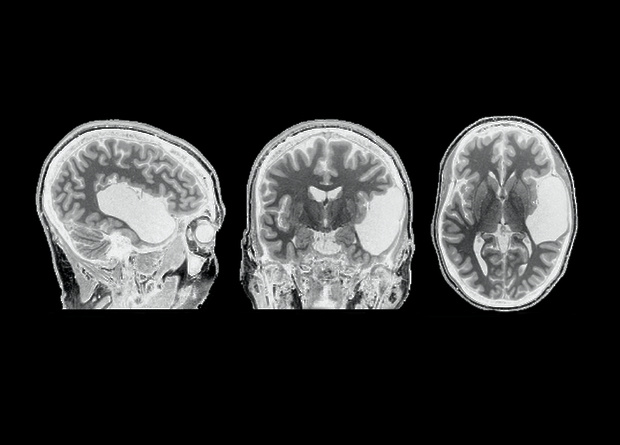

Наличие височной доли — обязательное условие для обработки языка лобной долей и, как следствие, — для появления языка в полушарии вообще. К такому выводу пришли американские ученые, которые изучили мозг женщины, в раннем возрасте утратившей височную долю левого полушария. Всю обработку языка на себя взяло правое полушарие, а вот в левом полушарии речь не обрабатывалась вообще — даже в лобной доли, которая осталась цела и выполняла другие функции, пишут ученые в журнале Neuropsychologia.

Основную роль в обработке языка в мозге человека играет нейронная сеть, объединяющая две находящиеся рядом части — лобную и височную долю. Эта связь начинает формироваться в период от года до трех лет, когда ребенок наиболее активно учится языку, укрепляется в полушарии (практически всегда — в левом) к четырем годам и развивается далее вплоть до взрослого возраста.

Чтобы ответить на этот вопрос, Эвелина Федоренко (Evelina Fedorenko) из Массачусетского технологического института вместе с коллегами изучила мозг женщины, которая живет без височной доли левого полушария головного мозга всю свою жизнь. Предположительно, ЕГ (так называют участницу исследования в статье) перенесла инсульт еще до рождения, но на ее развитии это не сказалось: у нее есть ученая степень, а помимо родного английского она практически